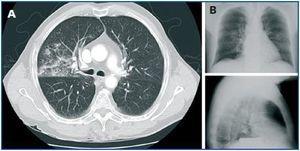

A blood test was carried out which revealed severe hyponatraemia 115mmol/l with plasma hypoosmolality 243mOsm/kg and hypouricaemia 2.4mg/dl, with normal blood potassium and renal function. There was elevated sodium loss in urine of 148mEq/l. The presence of hypothyroidism and adrenal failure was ruled out. The patient appeared to present SIADH and so water was restricted and hypertonic intravenous saline solution was administered. The patient¿s hyponatraemia progressively improved and his cognitive state normalised. When searching for the cause of SIADH, a brain MRI scan was carried out but no significant findings were made and a chest CT was performed which showed increased density of alveolar characteristics limited to basal segments of the right upper lobe that was very suggestive of pneumonia (figure 1A). However, a chest x-ray had been carried out on admission that did not show significant changes with regard to previous tests (figure 1B), the respiratory auscultation was normal and there were no leukocytes or other values that indicated infection. During admission the only significant symptom was an occasional fever of 37.2-37.4º C. Therefore, oral levofloxacin treatment was started and six days later a new chest CT showed significant improvement in the pneumonia. The urinary antigen tests for Legionella and Pneumococcus were negative. Gradually, the withdrawal of hypertonic saline solution was possible. It was administered until discharge following 15 days in hospital with water restriction, 6g per day of salt and 10mg/day torsemide. Plasma sodium levels remained stable at 131mmol/l. In the GP follow up, salt and diuretics were withdrawn and a month after admission the patient had fully recovered from SIADH, with plasma sodium levels 136mmol/l.

Figure 1.